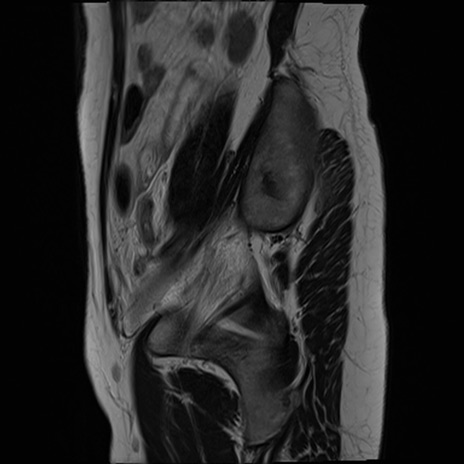

症例39 T2WI(矢状断像)

MRI(4日後)